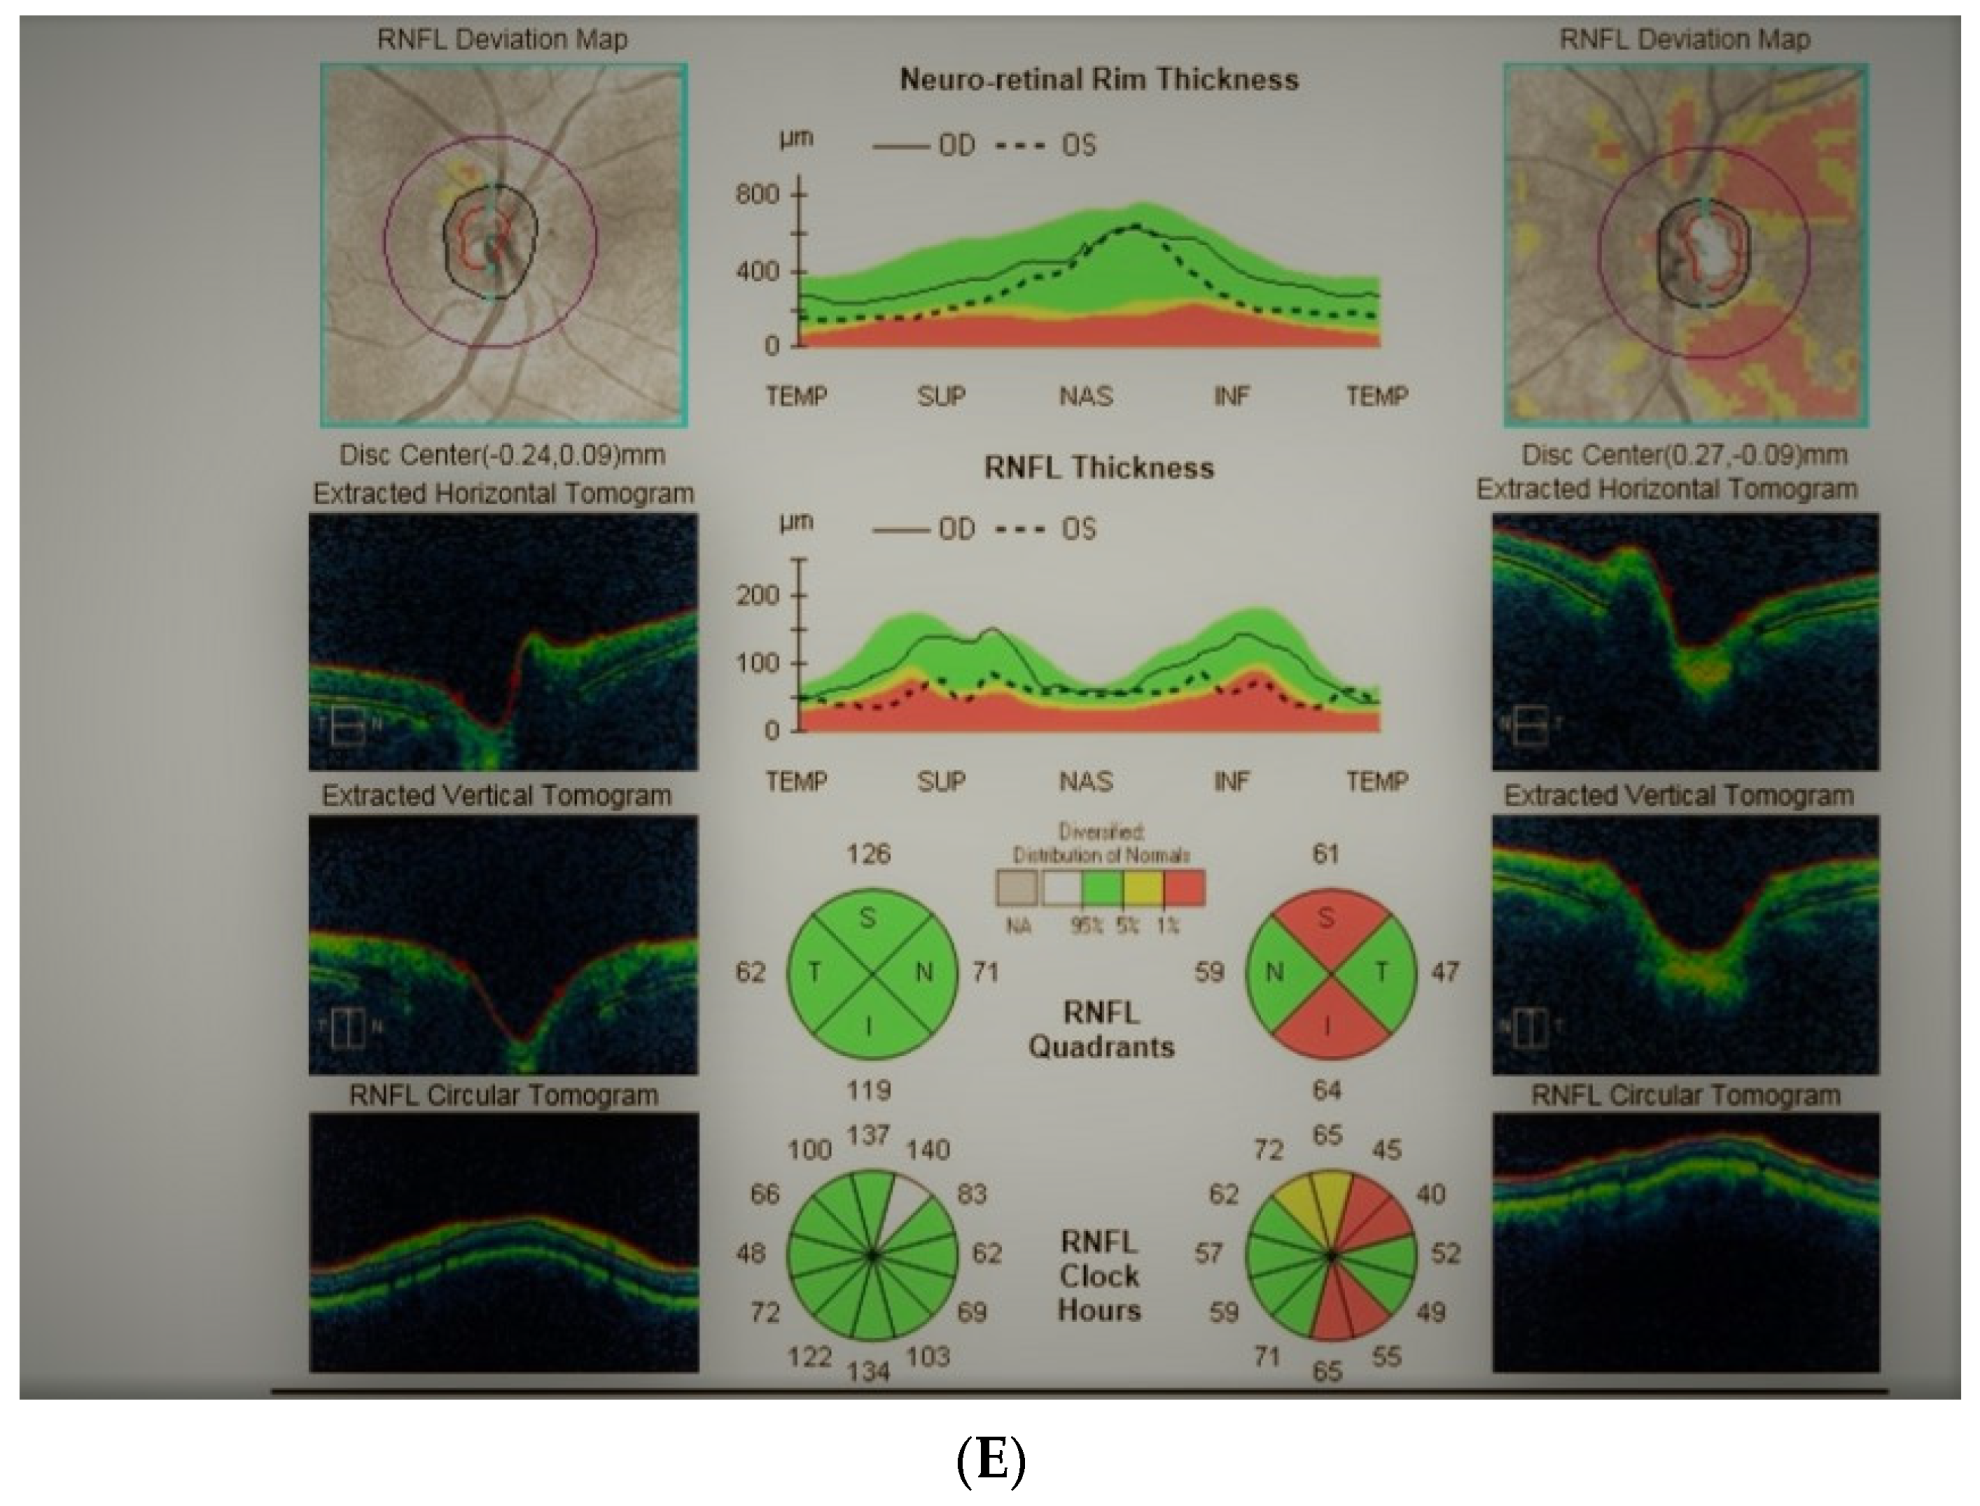

2.3. Case 3

2.4. Case 4

2.5. Case 5

- Lesions developing in association with an optic nerve develop unilaterally and are characterized by optic disc pallor, VF defects, and OCT findings (their morphology may differ from classical glaucomatous defects).